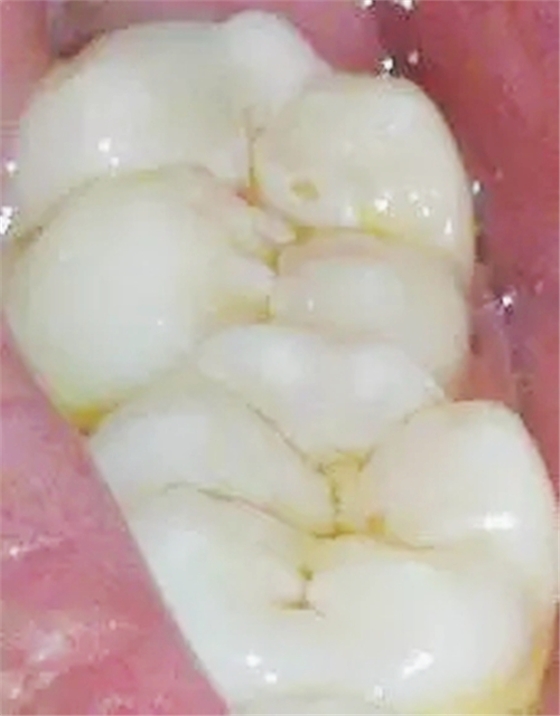

1,淺齲

齲壞局限于釉質(zhì)。初期于平滑面表現(xiàn)為脫礦所致的白堊色斑塊,以后因著色而呈黃褐色,窩溝處則呈浸墨狀彌散,一般無明顯齲洞,僅探診時有粗糙感,后期可出現(xiàn)局限于釉質(zhì)的淺洞,無自覺癥狀,探診也無反應。